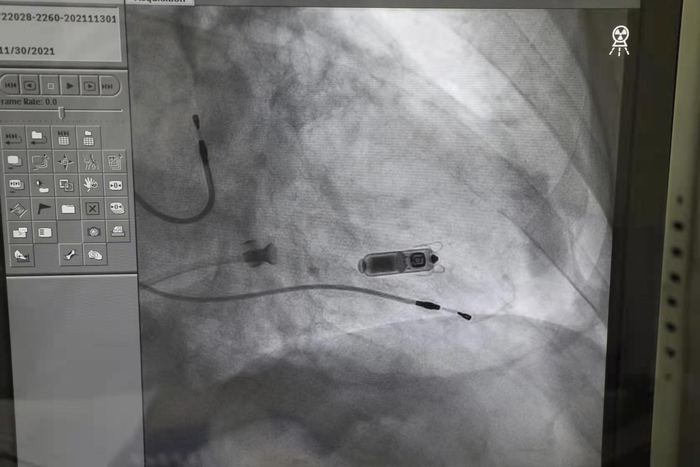

不能更换心脏起搏器的消息让林老伯很担心,也困扰着心内科的医生们,于是大家商议之后决定采用目前最新的无导线起搏器。术前,心内科团队与家属充分沟通,制定了缜密的诊疗方案,并邀请了上海交通大学附属第六人民医院心脏起搏电生理负责人李京波教授现场指导。11月30日下午,林老伯在局麻下接受了手术。医生通过股静脉穿刺,在导丝引导下,将起搏器沿着血管送入右心室,在选定了合适的位置固定,以及确认工作参数良好之后,医生成功释放了无导线起搏器,整个过程不到30分钟。

心内科主任王志华介绍,“用植入心脏起搏器来治疗心脏病的技术早已驾轻就熟,但这一方法对患者的身体状况、术后护理等都有较多要求,特别是当患者年龄较大或基础疾病较多时,经常让患者及家属陷入两难抉择中。这款无导线起搏器采用微创手术,术后6~12小时患者就可以下床活动,其优势还在于,体积比传统起搏器减小了93%,拥有超强的电池续航能力,同时兼容1.5t/3.0t核磁共振扫描的功能。由于它是直接植入在心腔内,除了股静脉穿刺口以外,无伤疤、无切口,不再有导线损伤和起搏器囊袋感染的可能,不影响患者术后双上肢活动,患者在植入后甚至感觉不到起搏器的存在。”

相较于传统的起搏器,无导线起搏器重量不到2克,体积仅有胶囊大小,通过导管以“微创方式”直接进驻右心室,不需要经过锁骨下静脉置入电极导线,无切口、无导线、无囊袋的特点,有效避免了起搏器囊袋破溃和感染,以及起搏导线磨损和断裂的风险 。